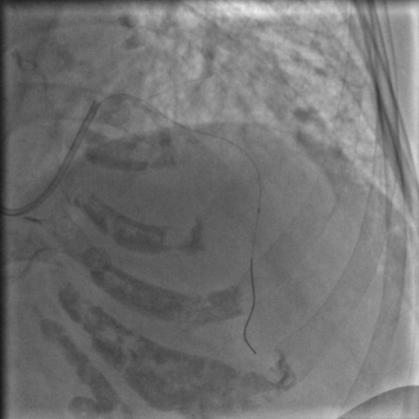

常规消毒、铺巾,再穿刺、放鞘管、送入造影导管、造影,一切顺利,造影结果如下:

图2

图3

图4

比我们想象中的要好,前降支中段闭塞,第一、第二对角支都还在,回旋支、右冠都还好,可以稍微松一口气。